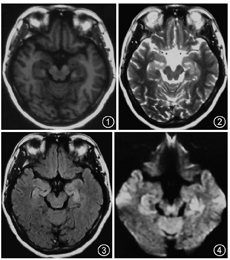

患者45岁,女性,既往体健。因"记忆力减退、精神异常3个月"余于2018年5月25日入滨州医学院附属学院。患者于2018年2月14日无明显诱因出现记忆力减退,表现为近期事件遗忘,反应尚可,可正常交流,2月16日后出现情绪不稳定,烦躁不安,时有喊叫及自言自语,交流困难,睡眠障碍,当时测体温38 ℃,遂就诊博兴县人民医院,颅脑MRI提示双侧海马硬化(图1,图2,图3,图4),血常规:嗜酸细胞百分比0%,单核细胞计数0.73×109/L,嗜酸细胞计数0×109/L,余未见明显异常。未予治疗,由于上述症状持续存在,于2月18日就诊胜利油田中心医院,行颅脑MRI+磁共振波谱(MRS)示双侧海马FLAIR信号增高,不除外海马硬化;MRS示左侧海马N-乙酰天冬氨酸(NAA)减低,NAA/肌酐、NAA/肌酐+胆碱比值降低。腰椎穿刺:颅内压190 mmH2O(1 mmH2O=0.009 8 kPa),脑脊液常规:无色透明,无凝块,潘氏蛋白定性(-),白细胞计数3×106/L,白细胞单核100%。脑脊液生化:蛋白0.41 g/L,葡萄糖3.8 mmol/L,氯化物122.3 mmol/L,腺苷脱氨酸0.3 U/L。新型隐球菌涂片、抗酸杆菌涂片阴性。脑脊液神经系统副肿瘤综合征系列:阴性。脑脊液自身免疫性脑炎系列:N-甲基-D-天冬氨酸受体(NMDA)型抗体、α-氨基-3-羟基-5-甲基-4-异恶唑丙酸(AMPA)1型抗体、AMPA2型抗体、抗富亮氨酸胶质瘤失活蛋白抗体、抗接触蛋白关联蛋白2(CASPR2)、抗GABAB受体抗体IgG阴性。血清自身免疫性脑炎系列:NMDA型抗体、AMPA1型抗体、AMPA2型抗体、抗富亮氨酸胶质瘤失活蛋白抗体、抗CASPR2、抗GABAB受体抗体IgG阴性。血清肿瘤标志物:鳞状细胞癌相关抗原、胃泌素释放肽前体、糖链抗原、神经元特异性烯醇化酶、细胞角蛋白19片段、甲胎蛋白、癌胚抗原、异常凝血酶原在正常范围,糖链抗原72-4 16.24 U/ml(高于正常值)。血常规:嗜酸细胞百分比0.3%,单核细胞计数0.64×109/L,余未见明显异常。诊断:病毒性脑炎、双侧海马硬化。给予阿昔洛韦、奥拉西坦治疗15 d出院,出院时无发热,情绪较稳定,仍近记忆力减退。5月15日受惊吓(打雷)后再次出现烦躁不安、时有吵闹,胡言乱语,无法交流,夜间不眠,测体温38.6 ℃,再次就诊博兴县人民医院,行颅脑CT未见异常,血常规示中性粒细胞百分比75.6%,淋巴细胞百分比19.1%,嗜酸性粒细胞百分比0.3%,余无异常,未予治疗。后再次就诊胜利油田中心医院,颅脑MRI+增强示双侧颞叶海马区斑片状长T2高信号,弥散加权成像(DWI)异常信号;增强后未见异常强化,除外脑炎可能(图5,图6,图7,图8,图9,图10)。胸部CT示右肺下叶占位,建议增强扫描,双肺间质性改变(图11,图12)。血常规:单核细胞百分比13.7%,余无异常。肿瘤标志物:鳞状细胞癌相关抗原8.60 ng/ml,神经元特异性烯醇化酶48.13 ng/ml。血T细胞绝对值计数:CD3+细胞绝对计数1 600×109/L,CD4+772×109/L,CD8+724×109/L,CD4+/CD8+:1.07,均在正常范围。诊断:右肺癌、颅内感染?认知障碍,给予阿昔洛韦、头孢曲松、吡拉西坦、丙戊酸、苯巴比妥钠等治疗7 d,体温波动在37.2~38.1 ℃,症状无好转,为求进一步诊治于5月25日入滨州医学院附属医院。入院体格检查:体温37.5 ℃,意识清楚,反应迟钝,交流困难,言语欠流利,记忆力、计算力、定向力减退,余神经系统体格检查无明显异常。相关检查回报:血清副肿瘤综合征检测:抗Hu、Yo抗体(+)。氟代脱氧葡萄糖(FDG)-正电子发射计算机断层扫描(PET)示右肺高代谢肿块,纵隔内高代谢淋巴结,考虑右肺癌并淋巴结转移;直肠近肛管处FDG代谢增高;甲状腺双侧叶病变,代谢不高;双侧基底节区FDG代谢略稀疏。右肺占位穿刺活体组织检查:小细胞癌,免疫组织化学染色:细胞角蛋白(CK)(+)、突触素(+)、嗜铬素A(+)、CD56+、甲状腺转录因子-1(+)、Ki-67阳性率约90%(图13,图14,图15,图16)。脑电图示背景为弥漫性低-中波幅不规则慢波,两侧无明显不对称,基线不稳(图17)。